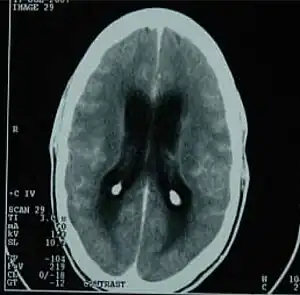

| CT scan showing tuberculous meningitis | |